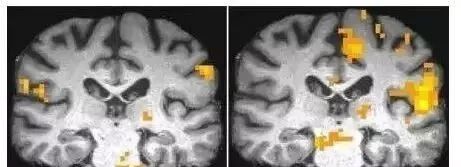

左图为健康大脑在前臂受到热刺激时的反应,右图为“海湾战争综合症2”病人的反应

他们的大脑含有大量的天冬氨酸,症状表现为精神错乱,注意力难以集中,突发性眩晕,情绪无法控制和波动剧烈,极度疲劳,身体麻木,或者持续性身体疼痛等等。经长期医学调查,这些症状完全符合阿斯巴甜后遗症。但是官方一直掩饰。